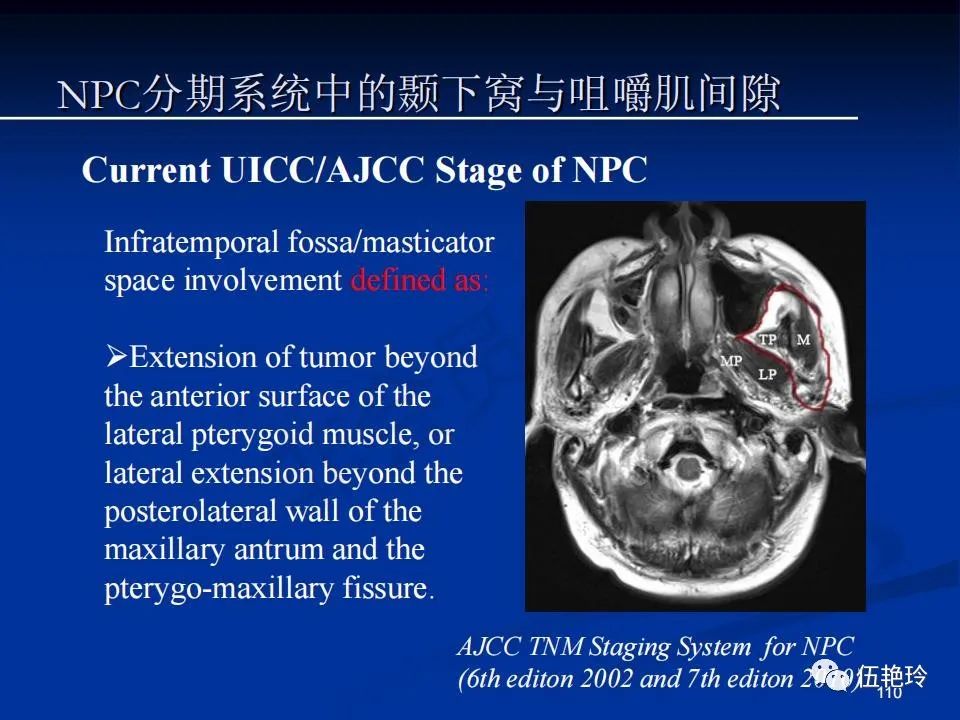

颞下窝与咀嚼肌间隙